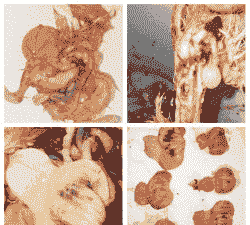

肠壁病变:肠壁由于粘膜脱落而变薄,肠壁质脆易碎,前段充满未消化的饲料碎片,后段充满橘黄色粘液样物质和未消化饲料,呈鱼肠子样、西红柿样、胡萝卜丝样。

大肠杆菌:大肠杆菌性败血症、出血性肠炎、大肠杆菌性肉芽肿等,表现为下痢、带有血液、肠黏膜出血和溃疡等。

梭菌:肉鸡梭菌性肠炎症状不明显,主要表现为饲料粪、溏便、水性腹泻等粪便异常,以及暂时性或一过性的增重缓慢或下降、饲料转化率减低、死淘率增加等非特异性症状。